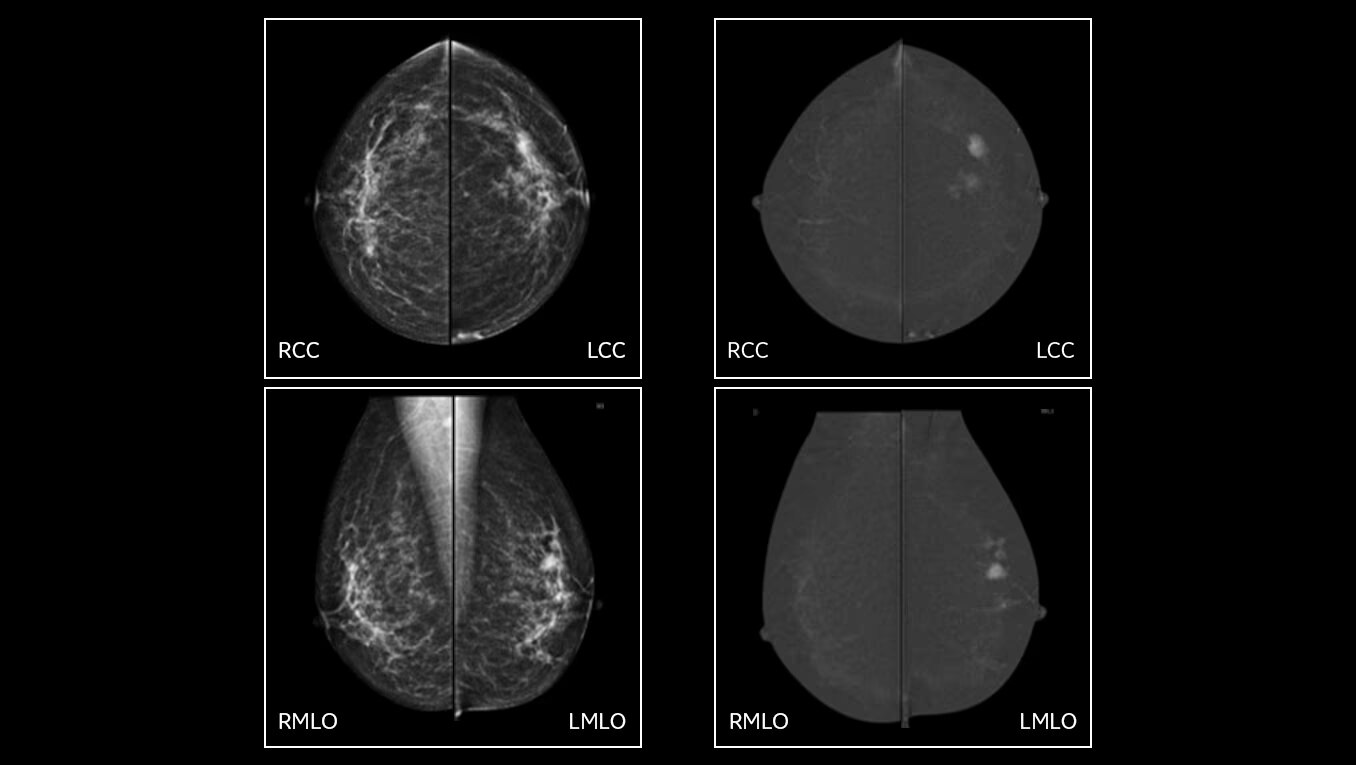

• CEM with Nira: thanks to the new recombination algorithm, the impact of the artifacts is significantly reduced for all readers and may improve confidence in the diagnosis5.